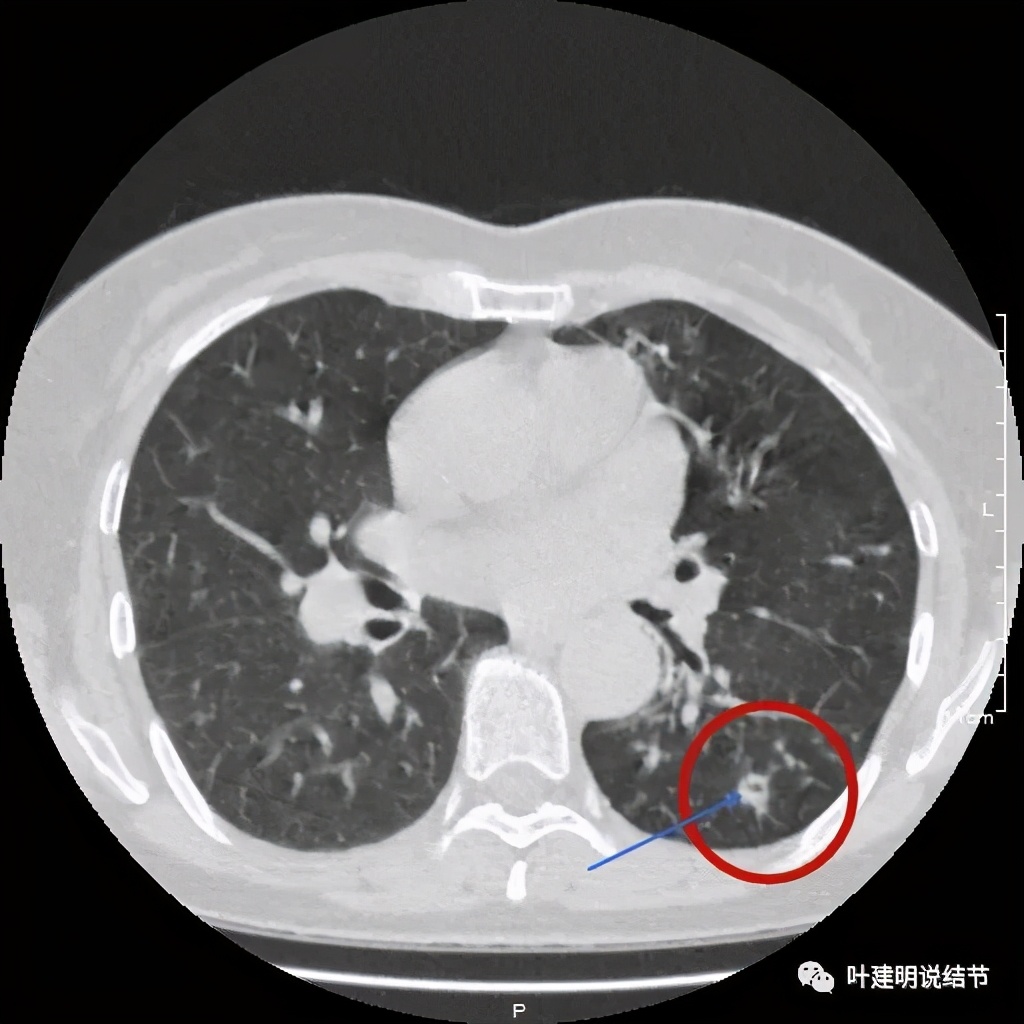

金华的某A,女性,56岁,去年8月份检查发现左肺下叶结节,是实性的,还中间有个空洞,我们说若磨玻璃结节伴空泡或空腔多为恶性范畴的,实性的也是可能性会大一些,但不如磨玻璃确切,因为结核、感染等也会类似的。我们先来看她当时的CT图像:

左下结节与血管关系密切,此层似磨玻璃结节,还夹在小血管之间,其中有血管紧贴病灶,略迂曲

上层见病灶偏实性密度,边缘不光滑

上图见病灶为实性,中间有小空洞,边上有血管进入病灶,靠后侧有棘突样

上图示病灶边缘不光滑,中间有小空洞

上图见病灶边上有血管

上图示病灶血管征较明显,有微小血管从不同方向走向病灶